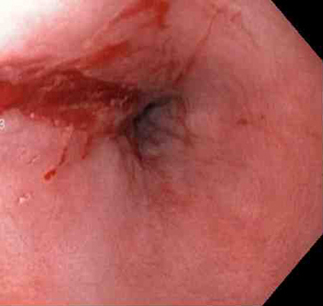

Laceração de Mallory Weiss com sangramento observada em retroflexão

Do acervo pessoal de Douglas Adler; usado com permissão